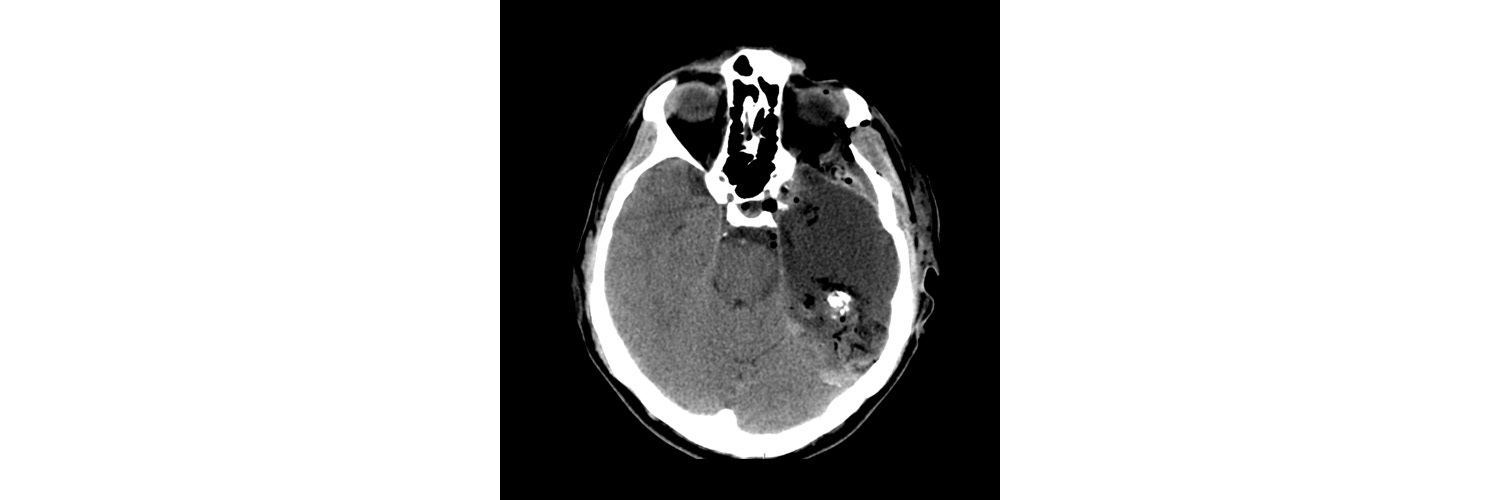

Рис. 16.18. Зрелая тератома. УЗИ